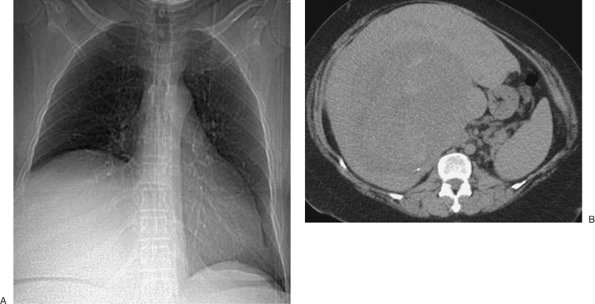

FIGURE 9-11. Malignant pleural effusion. A: PA chest radiograph of a 62-year-old woman with metastatic breast cancer who has had a right mastectomy and axillary node dissection (note surgical clips in right axilla; arrows) shows apparent elevation of the right hemidiaphragm. B: Lateral chest radiograph also shows apparent elevation of the right hemidiaphragm (arrows). The left hemidiaphragm is easily identified (arrowheads), as it is just superior to the stomach bubble. C: CT shows a large right pleural effusion (E) and metastatic breast cancer infiltrating the right chest wall (arrows). D: CT at a level inferior to (C) shows a metastatic soft tissue mass to the mediastinal pleura (arrow) and thickening of the mediastinal pleura (arrowheads).

When a large unilateral effusion is present (Fig. 9-11), four causes should be considered: (i) infection (empyema); (ii) tumor (primary bronchogenic carcinoma, mesothelioma, metastases, and lymphoma); (iii) chylothorax (secondary to tumor, most notably lymphoma, or ruptured thoracic duct); and (iv) hemorrhage (usually from trauma, whether iatrogenic or otherwise) (Table 9-2). Following drainage of a pneumothorax or pleural effusion, the re-expanded lung may become acutely edematous. The edema usually develops within 2 hours of re-expansion, can progress for 1 or 2 days, and resolves within 5 to 7 days. Large pleural collections with complete collapse

Malignant pleural effusions are usually the result of metastases (95% of cases) (16), with bronchogenic cancer accounting for 36% of cases, breast cancer for 25% (Fig. 9-16), lymphoma for 10%, and ovarian and gastric carcinoma for 5% or fewer (Fig. 9-17) (17). Although pleural effusion is often the major component of metastatic disease to the pleura, other findings include pleural nodules or extensive pleural thickening similar to that of mesothelioma. When the pleural metastases are unilateral, the CT findings may be indistinguishable from those of mesothelioma (18).